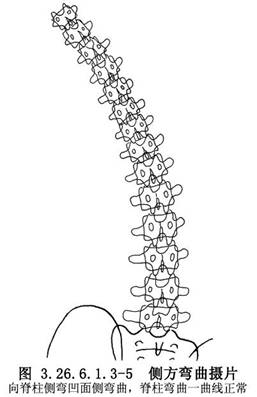

(2)攝臥位雙側彎曲脊柱正位相或懸吊位相。其意義是:瞭解脊柱側彎是結構性或是非結構性;了解結構性側彎(原發性側彎)的範圍,以確定脊柱融合的椎體範圍;瞭解畸形脊柱的彈性,估計術中器械矯形可達角度。向側彎凸側彎曲時結構性側彎的角度改變,大約與術中器械矯形可達到的角度一致(圖3.26.6.1.3-4~3.26.6.1.3-6)。